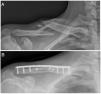

The patients underwent combined anaesthesia (regional block and general anaesthesia) and were placed in the beach chair position with padding behind the ipsilateral scapula. An anterior-inferior approach centred on the fracture site was used. Once the fracture was anatomically reduced, fixation was performed. A precontoured locking plate (Acumed, Hillsboro, OR, USA) was placed on the superior side of the clavicle (Fig. 1B). Interfragmentary screws were used for fragment fixation when a third fragment was present. At each plate fixation site, we used a minimum of three screws on each side of the fracture at each plating site.

A) Preoperative clavicle radiograph with 45° cephalic tilt showing a Robinson 2B2 fracture (displaced, comminuted and segmental) in a 17-year-old rugby player. B) Postoperative radiograph showing bone healing of the clavicular fracture three months after surgical fixation with a precontoured locking plate and three interfragmentary screws.